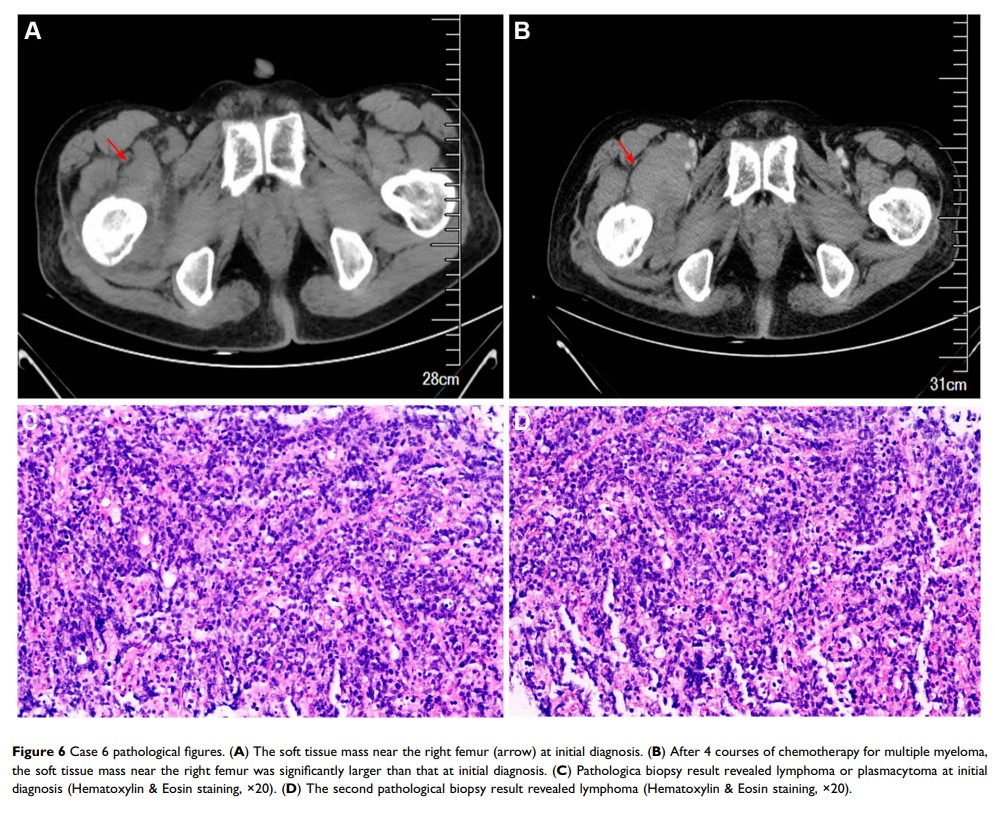

多发性骨髓瘤和其他原发性恶性肿瘤的同步存在:病例系列和文献回顾